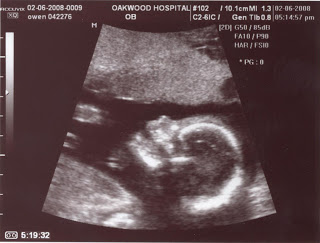

I realize all ultrasound pictures tend to look the same and I’m sure these are no exception. However, we had to laugh at Ruby’s smile at the end of her photo session.

Say cheese!